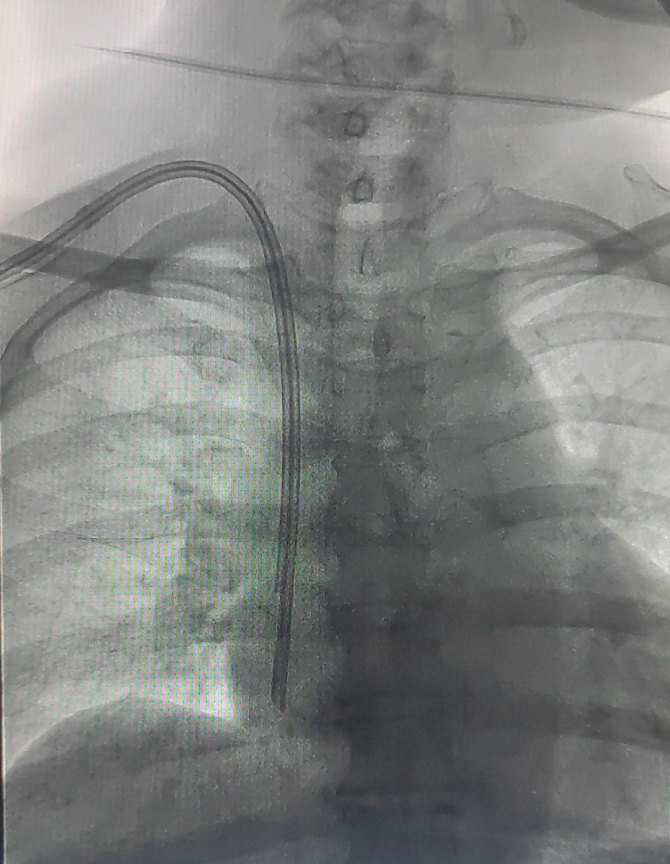

该患者由肾脏内科方敬爱教授医疗小组张紫媛、范彦君医生主管,诊断为尿毒症,行规律血液透析治疗,近期因心力衰竭、血压低等因素导致左侧自体动静脉内瘘堵塞,拟建立血管通路入院。经科室讨论后,本次手术在介入科DSA手术室进行,在实时透视引导下,清晰辨识患者右颈内静脉路径,一次性成功穿刺并将导丝送入下腔静脉。随后,建立皮下隧道,将带涤纶套的透析导管尖端精准定位至右心房中上部。术中全程严格无菌操作,患者生命体征平稳,术后无出血、感染、血气胸等并发症,次日透析时导管血流量充足,达到预期治疗效果。